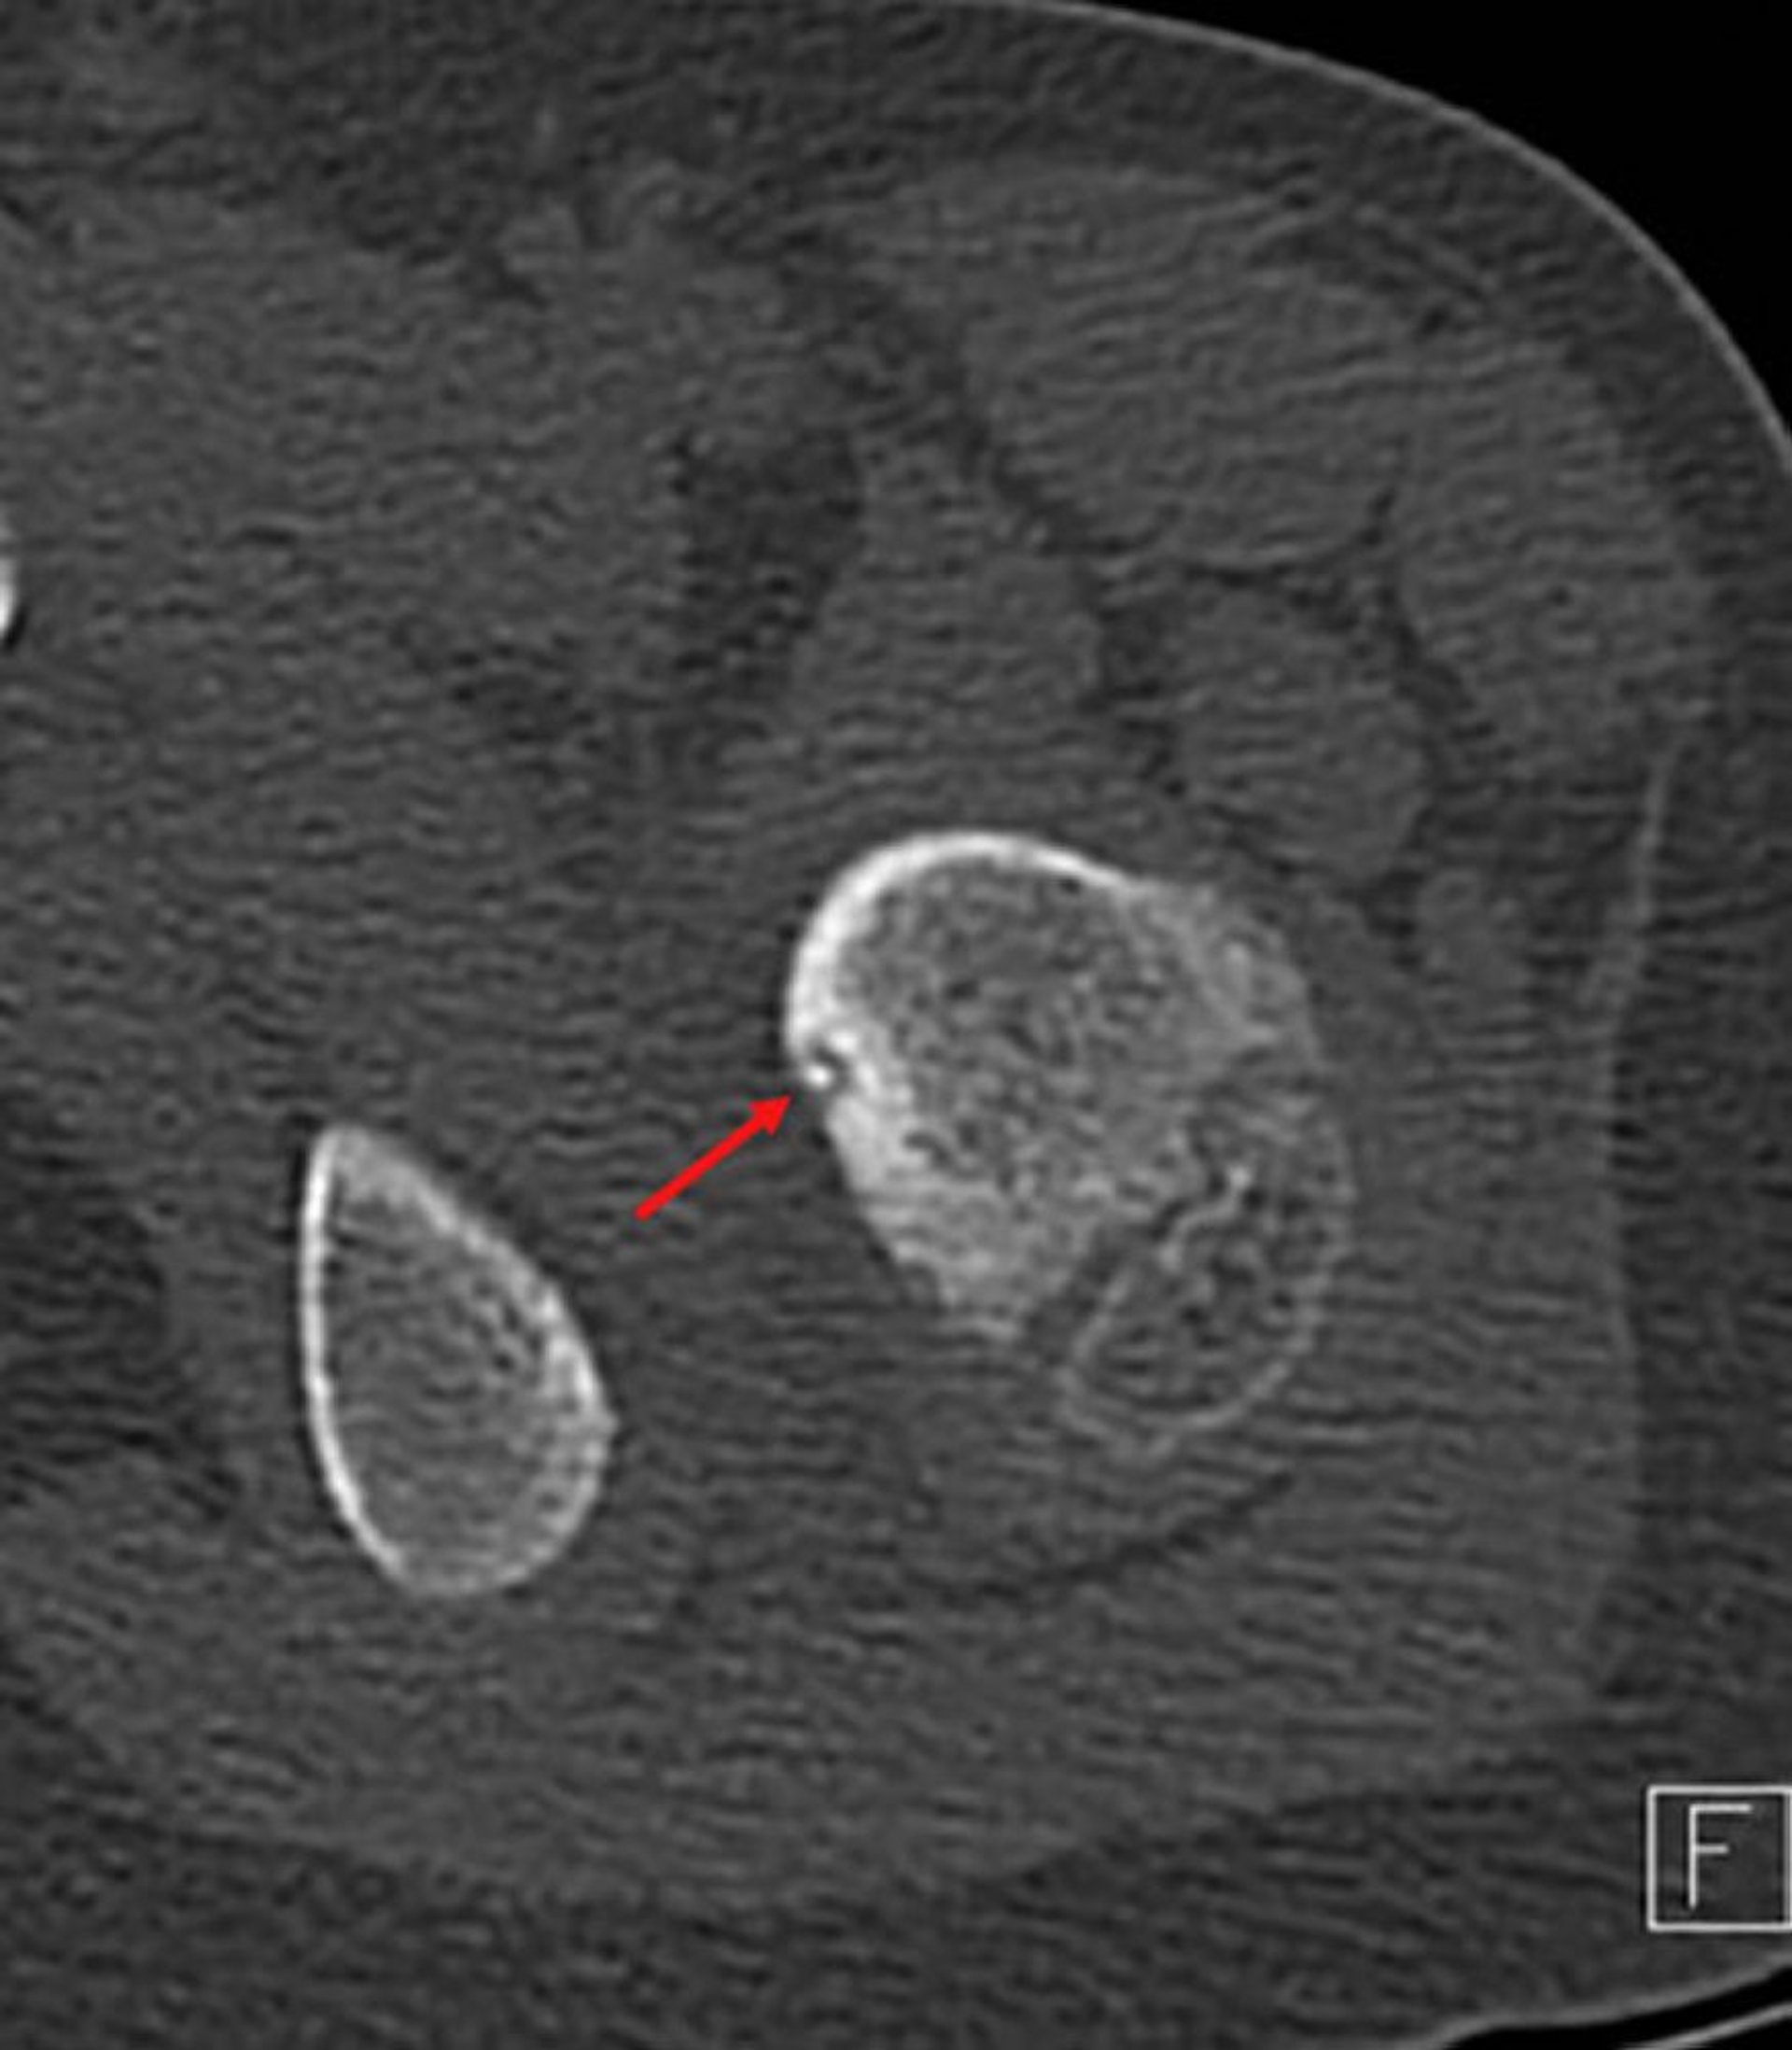

Osteoma osteoide

Imagen axial de TC del fémur proximal (el hueso adyacente es la rama pelviana) que muestra el nido radiolúcido típico con calcificación central (flecha) y el borde reactivo circundante en un niño con dolor en la cadera izquierda.

Image courtesy of Michael J. Joyce, MD, and Hakan Ilaslan, MD.